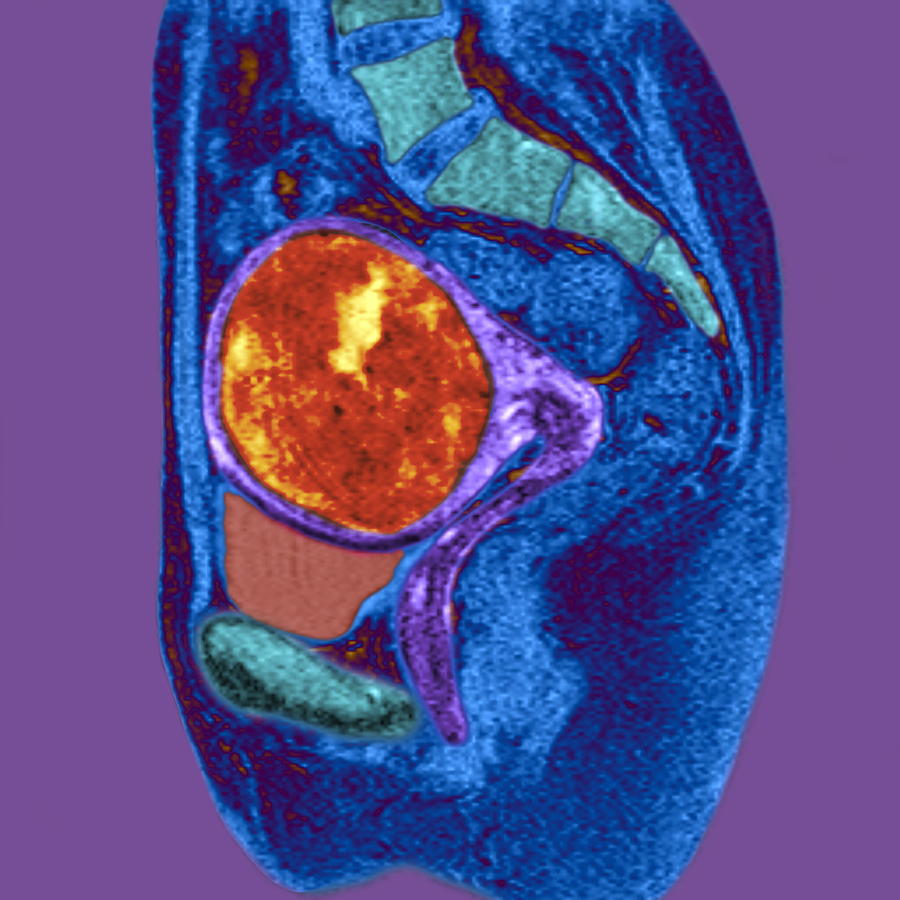

Uterine Fibroid, Mri Scan Photograph by Du Cane Medical Imaging Ltd

Pelvic MRI for Fibroids – Why You Need an MRI to Detect Fibroids

Uterine Fibroid, Mri Scan Photograph by Du Cane Medical Imaging Ltd